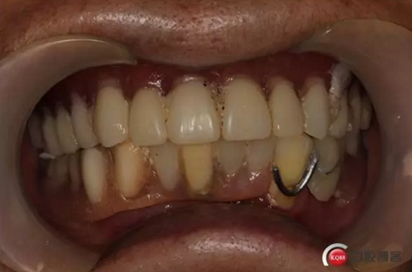

6)數(shù)字化義齒制作中心制作完成修復(fù)體臨時(shí)冠橋試戴,合適后完成最終二氧化鋯橋修復(fù)體

健康的牙齦袖口

戴牙:試戴,拍片確定邊緣密合后調(diào)整咬合,試戴一周后患者適應(yīng),咬合良好,基臺(tái)加力30N.CM,粘接劑粘固,去除多余粘結(jié)劑,拍片確定有無(wú)粘接劑殘留,并進(jìn)一步微調(diào)咬合

6)6個(gè)月后復(fù)查,修復(fù)體密合性均良好,修復(fù)效果符合預(yù)期,醫(yī)囑患者做好口腔衛(wèi)生預(yù)防種植體周圍炎